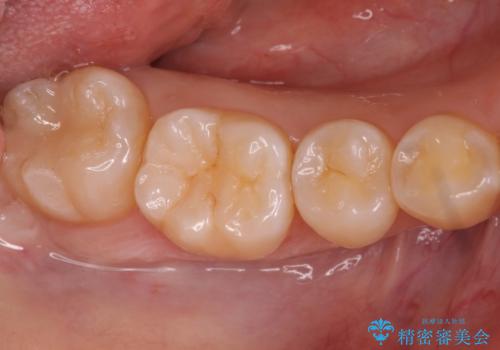

奥歯の黒ずみが気になる セラミックインレーでの治療

- 奥歯の黒ずみが気になるとのことで来院されました。

樹脂での治療も考えましたが、材料の劣化を避けるためにセラミックインレーでの治療をすることとなりました。

- 右下7 セラミックインレー 77,000円費用は治療当時の料金となります

セラミックは樹脂が含まれていないため劣化の面では非常に優れた材料です。